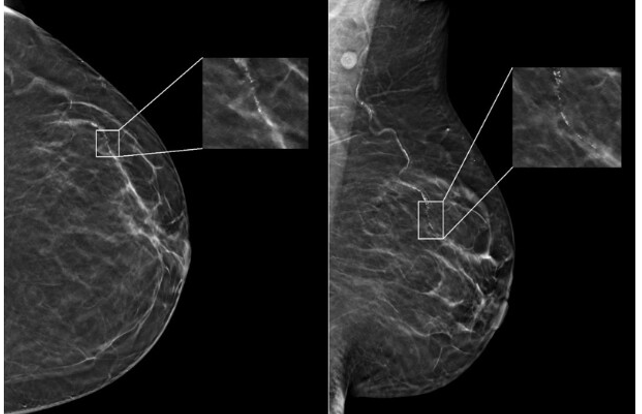

Dans le Parlons IA de la semaine 21, découvrez comment l’intelligence artificielle permet aux compagnies aériennes d’optimiser la gestion de leurs vols. Apprenez-en davantage sur une étude menée grâce à l’IA, révélant des différences dans les structures cérébrales entre les hommes et les femmes. De plus, familiarisez-vous avec DEPLOY, un outil d’IA capable de classer les tumeurs cérébrales en 10 sous-types principaux avec une précision de 95 %.